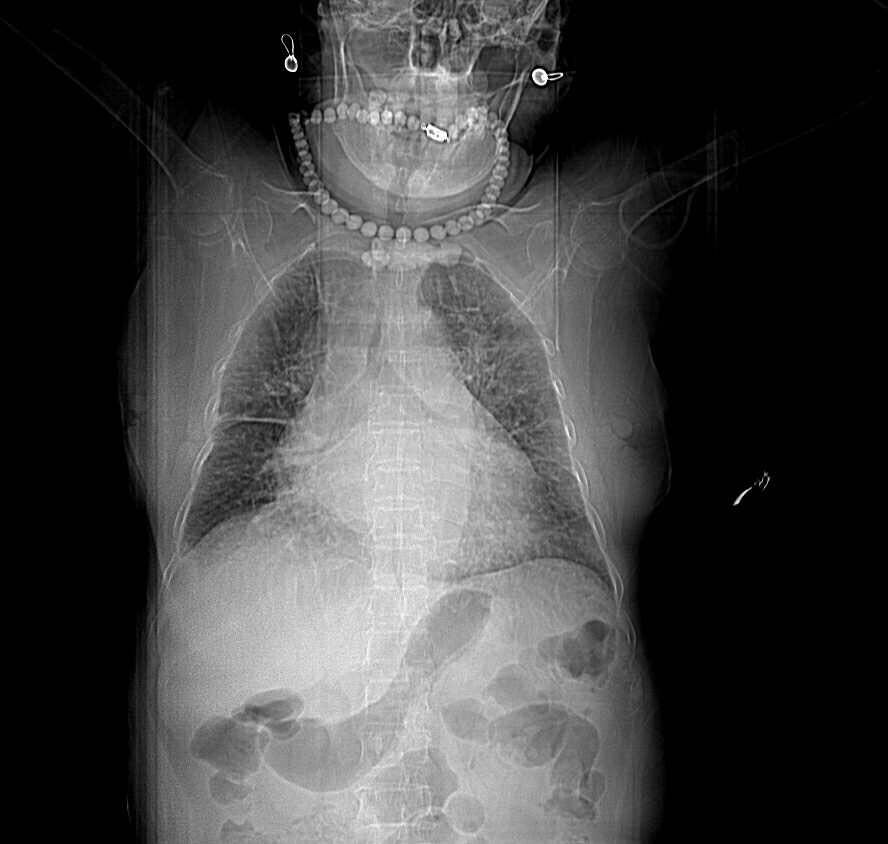

女,75岁。 呼吸困难10余天 加重2小时憋喘貌。双肺呼吸音减低,闻及满布湿罗音。患者既往冠心病,高血压十五年。双下肢水肿。无发热,少量白痰。白细胞正常,红系减少明显。